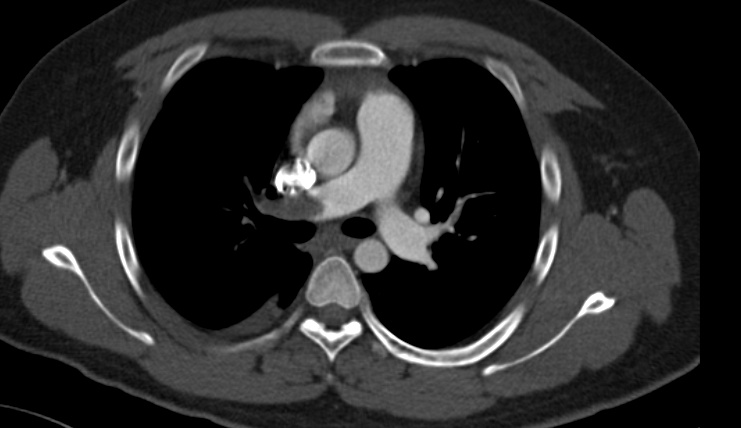

2020年7月,小张(化名)因突发胸痛、呼吸困难、咯血收入云南省阜外心血管病医院(简称云南省阜外医院)肺血管与综合内科住院治疗。后经肺血管造影(CTPA),V/Q肺通气血流灌注核素显像,右心漂浮导管等确诊为:右肺动脉主干巨大血栓、肺动脉高压。并对血栓产生的原因进行了仔细检查,发现他是一个蛋白s,蛋白c缺乏的易栓症病人。

针对患者的血栓右侧为主,须排除肺血管肿瘤的可能,随即进行了PETCT检测,发现患者为为慢性血栓。